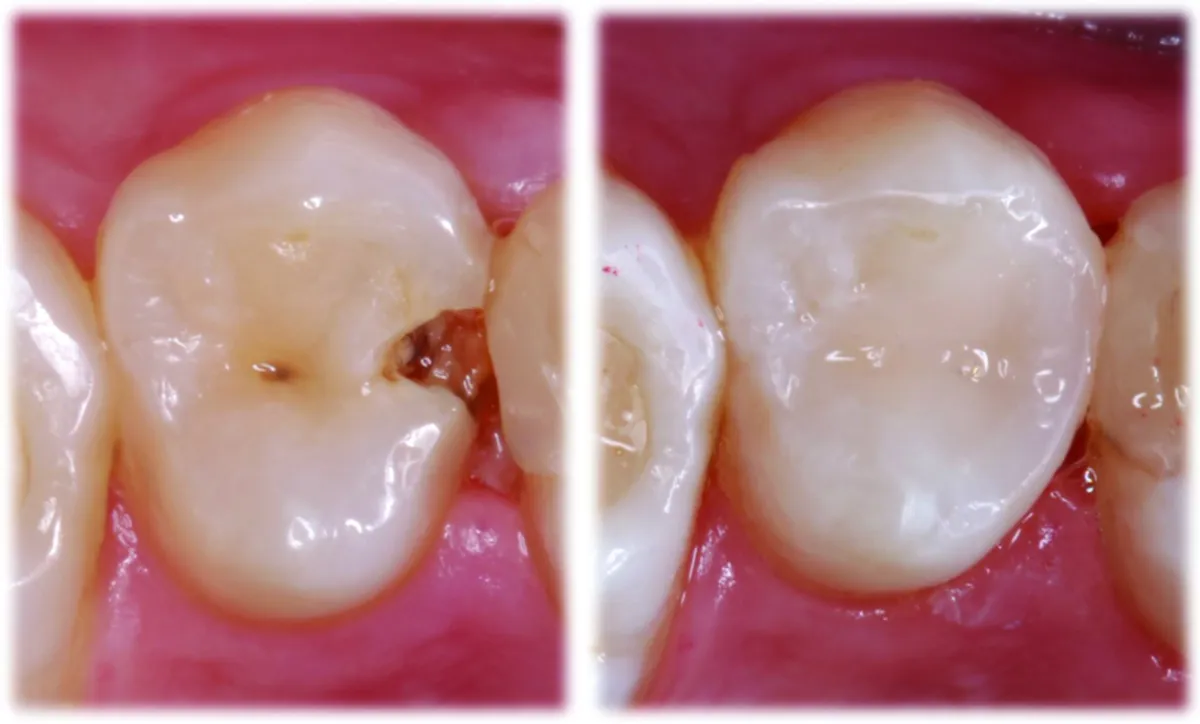

Case Details

Interproximal caries is the most common type of dental pathology and therefore interproximal fillings in the posterior area are the most common restorative procedures. Restoring adequate cervical contour and tight interproximal contacts are of utmost importance for long term stability of such restorations. Open contacts and cervical overhangs lead to development of secondary caries and periodontal pocket.

The presented case is removal of the interproximal caries with deep cervical margin and wide buccal and palatal extensions. After the cavity preparation and isolation with the rubber dam, Garrison matrix with extension, Blue (small) wedge and Wide Prep (green) ring were placed. The wide extensions of the ring allow to restore adequate buccal and palatal contours of the tooth. The sectional matrix is easily shaped to restore proper anatomy and tight contacts. The rest of the cavity is filled with respect of the simplified tooth anatomy. Rough polishing and contouring were done under the rubber dam isolation. After the removal of the rubber dam the procedure ends with fine polishing and occlusal corrections.